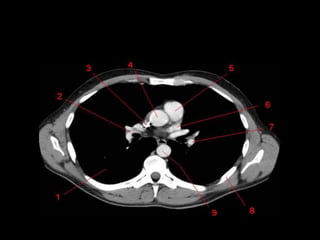

Mediastino Médio

• Pericárdio e seu conteúdo, arco aórtico e as

grandes artérias proximais, as artérias e veias

pulmonares centrais, traquéia, brônquios

principais e linfonodos.

• Nervo frênico e vago não são visíveis a TC.

• Janela Aortopulmonar

– Tecido adiposo, linfonodos, ligamento arterial e

nervo laringeo recorrente.

Tronco Pulmonar e Janela Aortopulmonar

• Inferior ao

arco aórtico e

a Esquerda

da traquéia

• Medial:

Traquéia, BPE

esofago.

• Lateral:

Superficie

Pleural do

lobo superior

esquerdo.

Hilo Pulmonar

• Artéria Pulmonar Direita passa anterior ao brônquio

principal direito

• Artéria Pulmonar Esquerda passa superior ao brônquio

principal esquerdo.